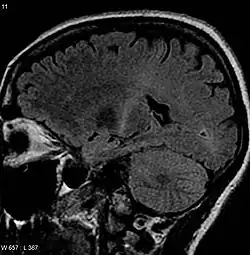

An MRI of the brain looking at a person from side-on that shows increased T2 signal as a white region in the posterior part of the internal capsule that can be tracked to the motor cortex, consistent with the diagnosis of ALS